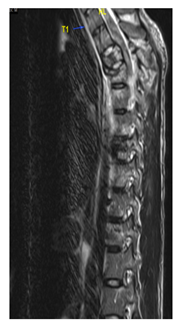

A 26-year-old male, soldier, involved in road traffic accident on 27th of August 2019 in the southern region of Saudi Arabia. The patient was transferred to the military hospital in the south and they stabilized him there and then transferred to our hospital on 29th of August 2019. The patient had multiple injuries: T3–T4 spinal fracture (Figure 1), left proximal humerus fracture (Figure 2), 8th & 9th rib fractures with multiple lacerations. He underwent for left open reduction and internal fixation of the proximal humerus by using Proximal Humerus Internal Locking System "PHILOS" plating on 03-Sep-2019 (Figure 3A & 3B). Also, the patient underwent spinal fixation for the fracture from T1 to T8on 05-Sep-2019 (Figure 3C). One month postoperatively, he started to have left big toe gangrene and vascular surgery was consulted. They recommended doing CT angiogram of the aortic arch and echocardiogram. CT showed that left pedicular screw of T6 and T8 appear lateral to the pedicle and the tip of the screws abutting the medial wall of the descending thoracic aorta at the posterior mediastinum but there is no obvious surrounding active haematoma or aortic thrombosis (Figure 4A & 4B). Pre-operative assessment and measurement were done and it was showed: Whole length supposed to be covered: 10cm, Proximal landing zone on the sagittal view: 2.67cm, Distal landing zone on the sagittal view: 1.83cm, Proximal axial: 2.14cm x 2.11cm, and distal axial: 1.92cm x 1.78cm.

Figure 1 MRI sagittal cut of cervical and dorsal spine showed a compression fracture of T3 vertebral body with 50% reduction in its height and compression fracture of T4 involving only the superior endplate with retro-pulsed posterior vertebral margin of T3 causing cord contusion.